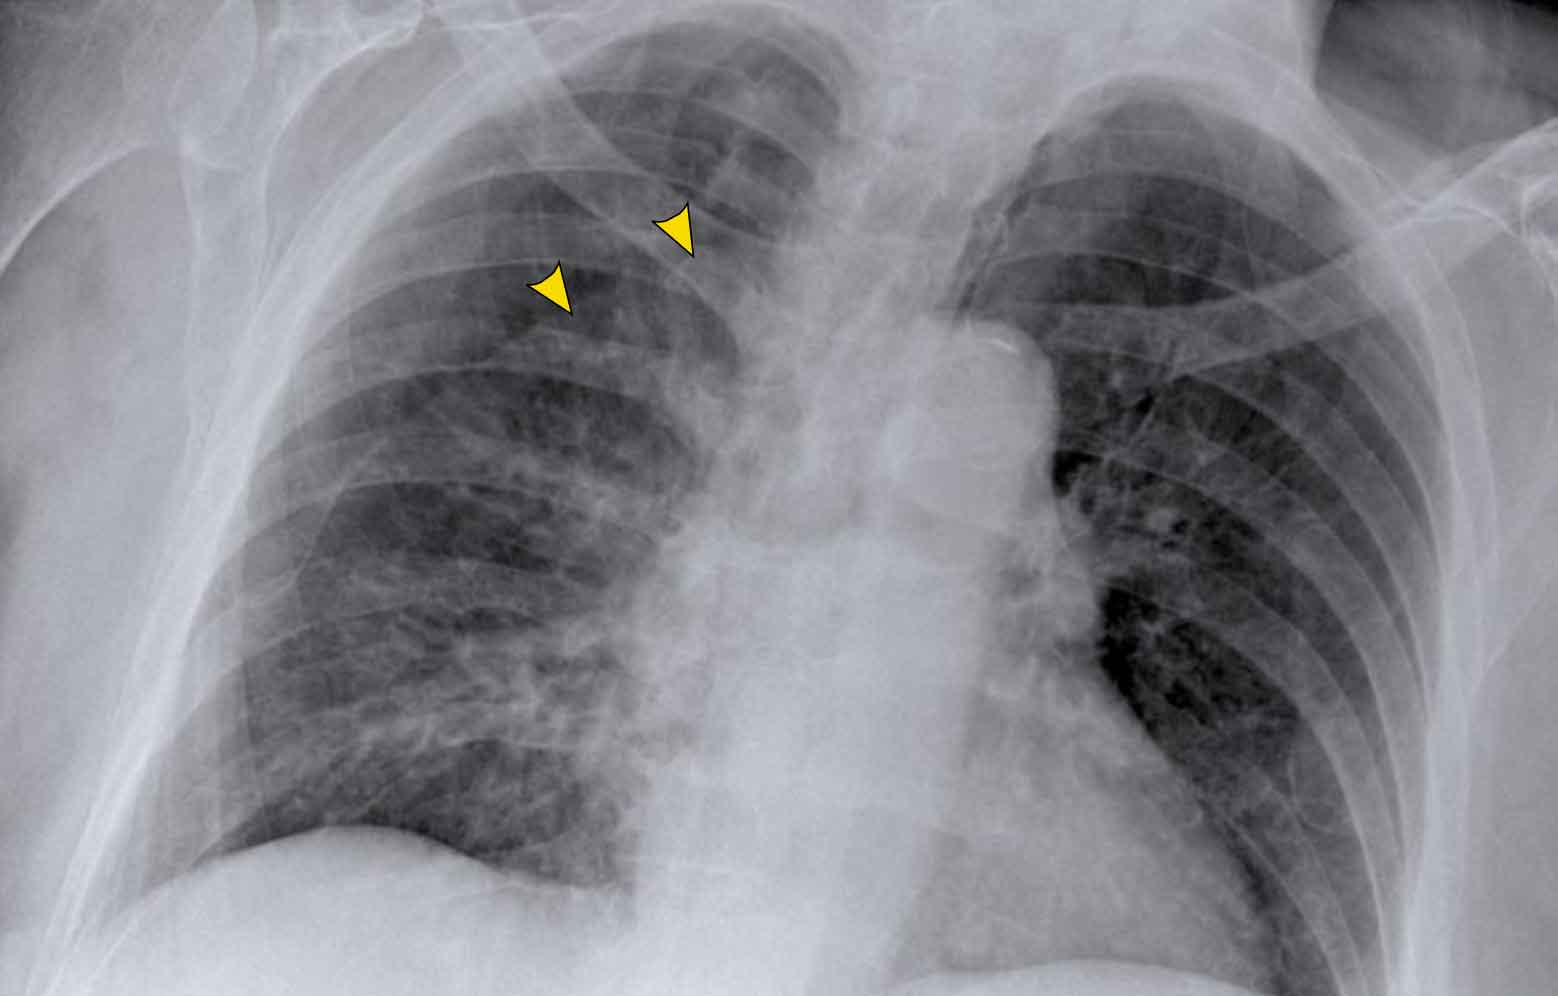

Hidden area (5): Mass Behind the First Rib

In some patients, an accessory joint at the anterior aspect of the first rib may simulate a mass, as we learned earlier.

However this area is also a "hidden zone", where true lesions can be masked.

• In this case, a small lung carcinoma was obscured by the left first rib on the PA view.

• On the lateral film, the lesion is visible in the retrosternal space.

Continue with the PET-CT...

Subsequent PET-CT imaging confirmed a hypermetabolic tumor (arrow), with metastases to the bone and liver.

• Diagnosis was confirmed via biopsy of an osteolytic metastasis in the iliac bone.

Incidental Thoracic Finding

• A subtle density is visible over the first rib in the left upper lobe, located in the so-called "hidden area".

• This was subsequently diagnosed as a primary lung carcinoma.